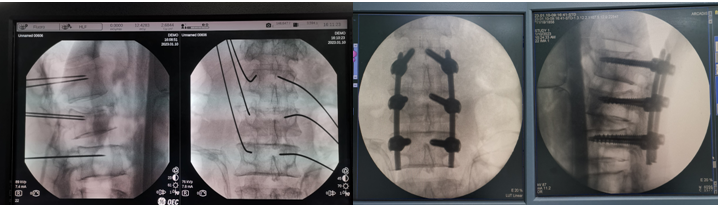

在刘时璋主任精心筹备、悉心安排下,术前手术医生团队和手术机器人技术保障团队密切协作,详细分析了患者腰椎CT资料,精确规划了椎弓根螺钉通道位置及各项参数,重建模拟椎弓根螺钉植入后三维图像,并不断优化方案使其更精准、安全,并进行了手术机器人使用的术前演练。手术当天,常彦海主任医师和陈明副主任医师共同为患者实施了手术。术中,借助C臂获取患者腰椎正侧位影像及标记定位,将其传入机器人系统与患者术前腰椎CT质料匹配映射,确定了每个螺钉的实际穿刺通道,通过机械臂在压力监测和光学追踪引导下依次钻入导针,最后精准植入6枚椎弓根螺钉。脊柱周围毗邻重要神经和血管,椎弓根螺钉通道空间有限,常规经皮植钉技术风险大,容易发生神经损伤等并发症,且术中需要反复透视,手术机器人很好弥补了这些弊端,相当医生有了“透视眼”和“第三只手”,使手术操作更加智能化、精准化。